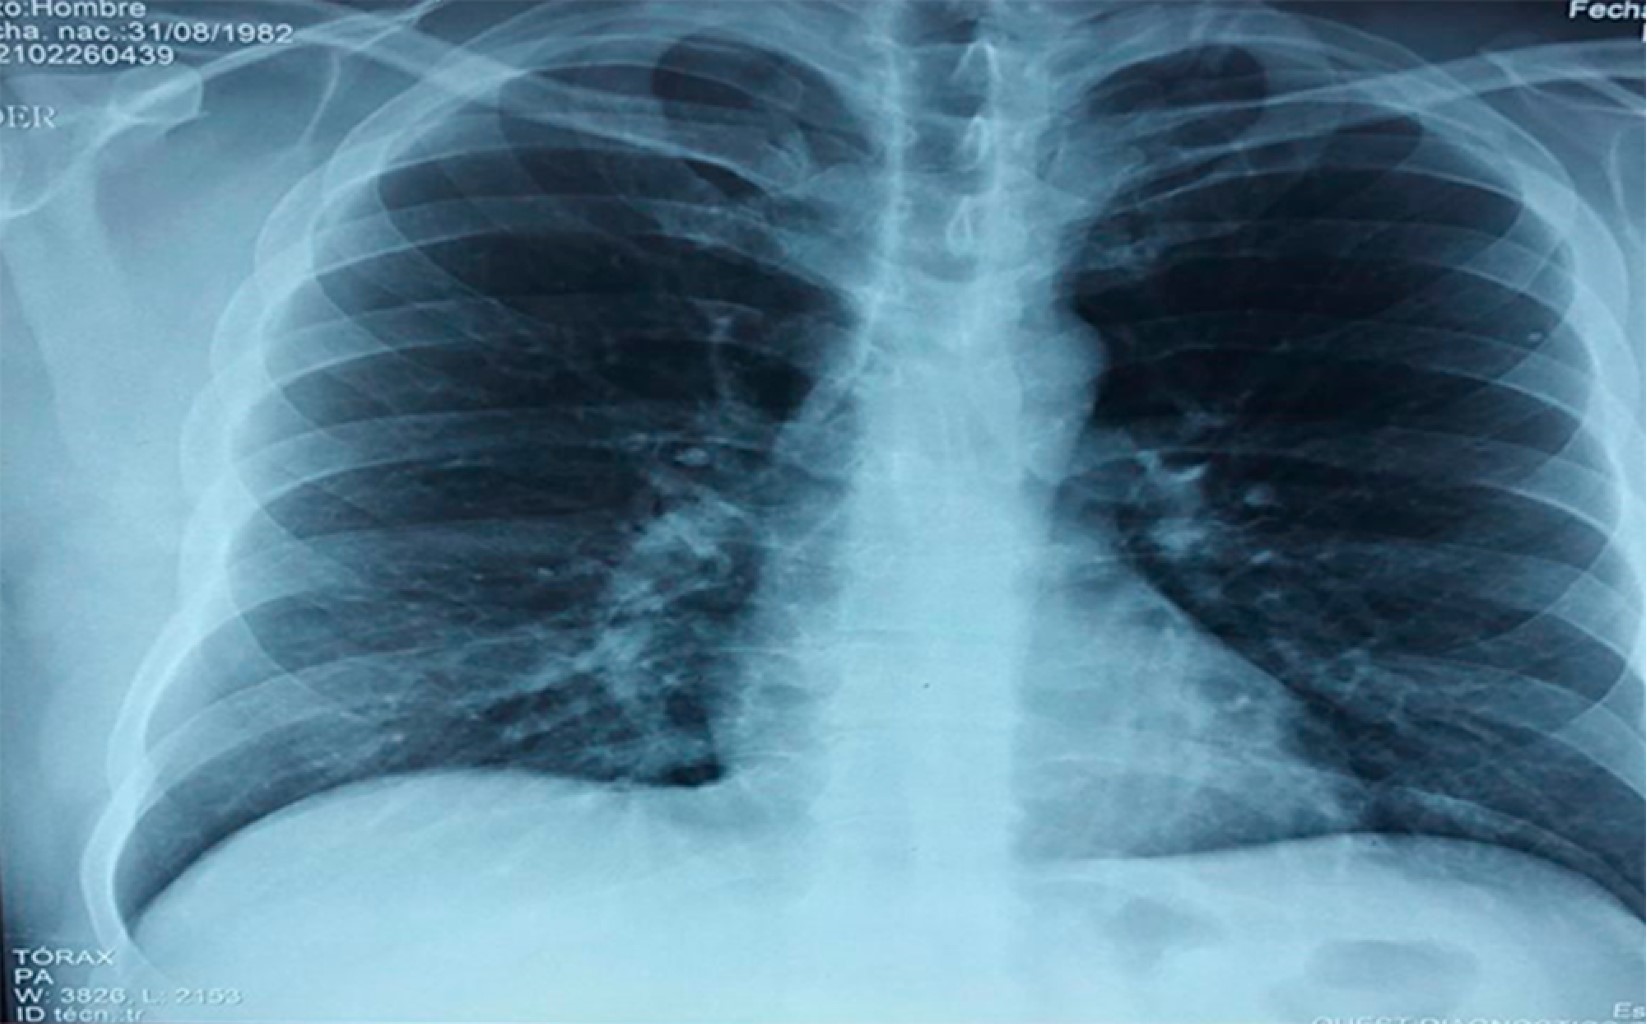

Masculino de 38 años de edad destaca dedicación a la ganadería caprina, sin uso adecuado de equipo de protección personal. Acudió al servicio de urgencias por cuadro clínico de un mes de evolución con presencia de fiebre de predominio nocturno de 39 oC, duración de tres horas, astenia, adinamia, con signos vitales tensión arterial:130/80 mmHg, frecuencia cardiaca:100 lpm, frecuencia respiratoria: 20 rpm, temperatura: 37 oC. A la exploración física sin existencia de adenopatías palpables, sin alteraciones pulmonares ni cardiacas, abdomen sin alteraciones. En la analítica hemoglobina: 17 g/dL, plaquetas: 362 × 109/L, leucocitos: 14.8 × 109/L, neutrófilos: 10.3 × 109/L, PCR SARS-CoV-2 negativa, examen general de orina y urocultivo negativos, IgG Coxiella fase I negativo, IgG Coxiella fase II positivo, IgM fase I Coxiella positivo 1,256 U/mL, IgM fase II Coxiella positivo 116,384 U/ml, radiografía simple de tórax (Figura 1), tomografía simple de tórax (Figura 2). Ecocardiograma transtorácico (Figura 3). Se inició tratamiento con paracetamol 1 gramo intravenoso cada ocho horas y doxiciclina 100 mg vía oral cada 12 horas durante dos semanas (14 días) con mejoría.

Figura 2